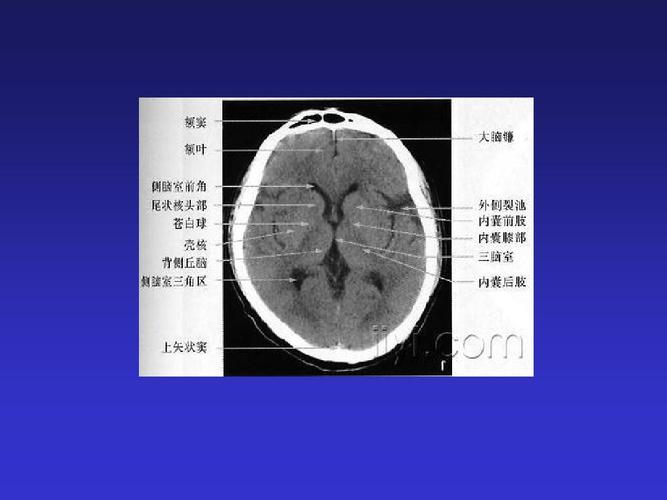

头部CT解剖

头部CT解剖,头部CT解剖

头颅ct断层解剖

影像医生必须掌握的头颅ct解剖与常见出血梗死判读

头颅ct影像解剖

头颅ct 解剖图谱,人手一份

正常头颅ctppt

头颅ct解剖

颅脑ct解剖